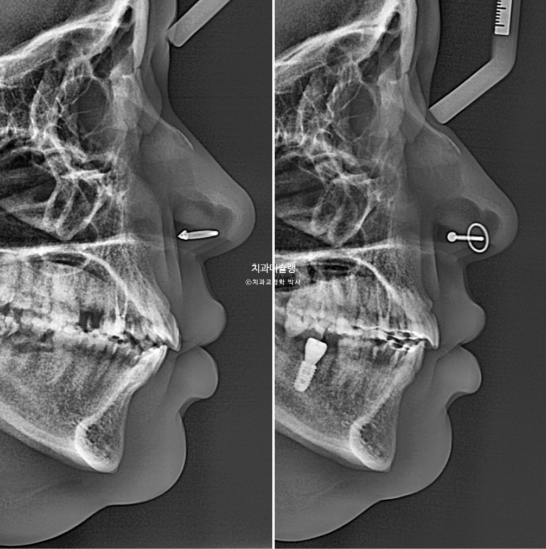

In the area of the missing mandibular molar, the site had been left untreated for a long period. As a result, the opposing tooth (indicated by the blue arrow) had supra-erupted.

For proper implant placement, this opposing tooth needs to be intruded through orthodontic treatment.

At this stage, the implant fixture was first placed in the mandibular posterior region, followed by intrusion of the supra-erupted opposing tooth.

For effective intrusion, a temporary orthodontic mini-screw was placed in the palate.

After successful intrusion of the opposing tooth, the implant crown was delivered in December 2025, and the orthodontic treatment was completed.

Now, let’s take a look at the facial profile changes.

The lip protrusion has also been resolved.

Even in cases involving extraction of four premolars, we carefully control the treatment to avoid excessive retraction that could result in an aged appearance.